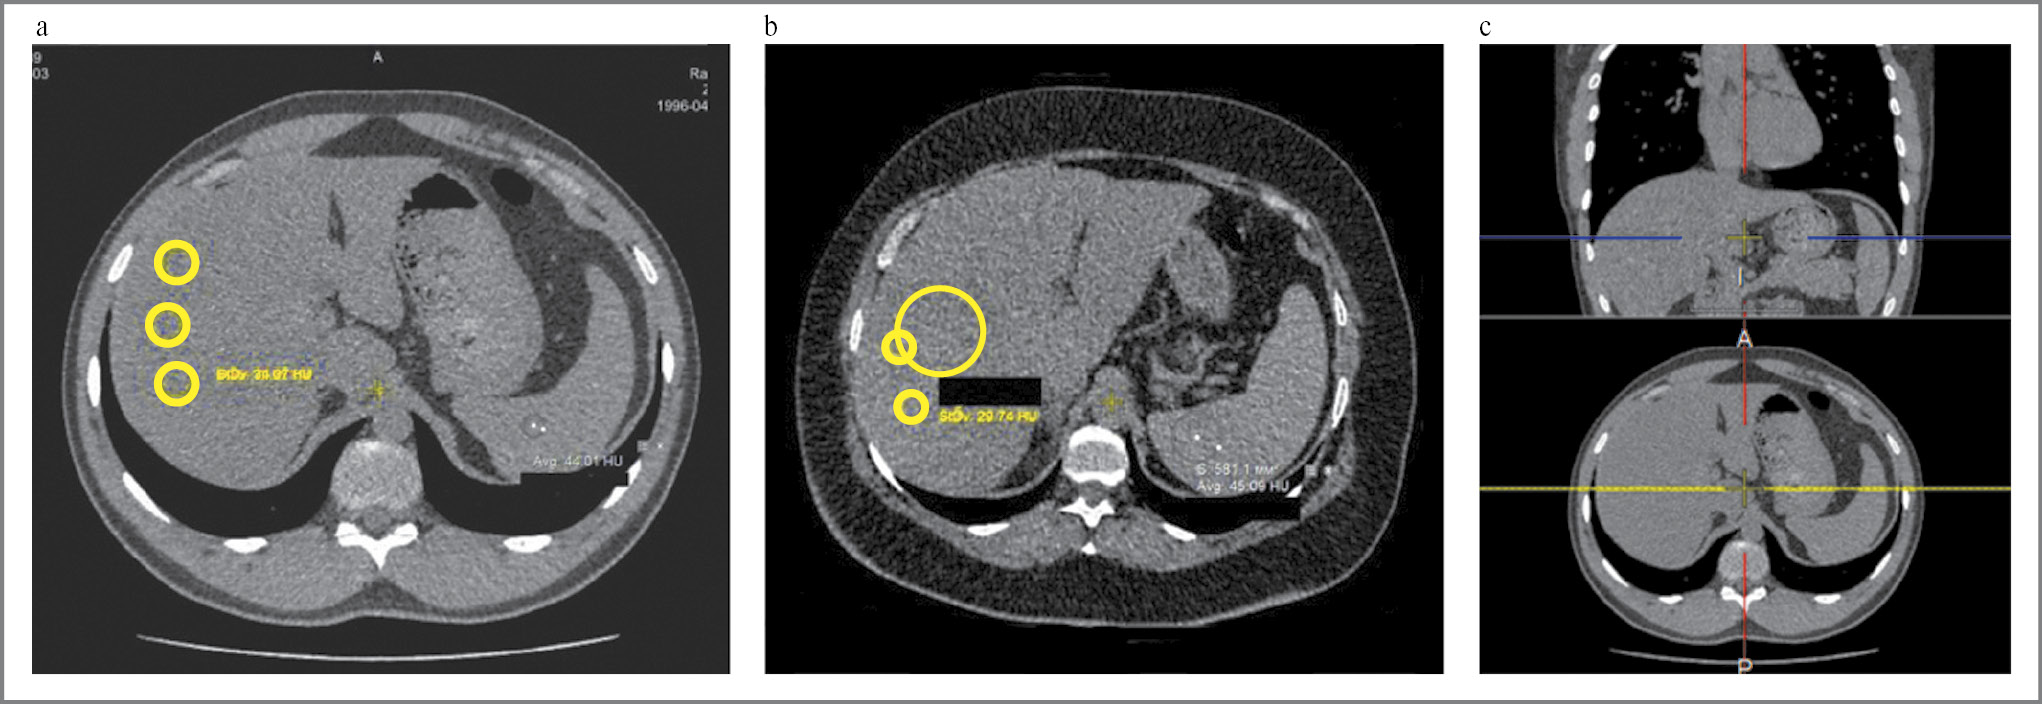

Врач-рентгенолог, ослепленный к результатам физикального и лабораторного обследований, вручную изучал ROI площадью до 1,5 см на КТ-изображениях. Для измерения ослабления сигнала в печени и селезенке ROI были расположены таким образом, чтобы исключить макроскопические сосуды печени, желчные протоки и любые очаговые поражения печени, и находились на расстоянии не менее 5–10 мм от периферии печени. Все ROI размещены в разных местах правой доли печени между сегментами печени V, VI, VII и VIII, которые определены в соответствии с классификационной системой Куино (Couinaud classification) [28]. Ослабление плотности печени измеряли путем нахождения среднего между максимальным и минимальным полученным значением HU, показатель ослабления селезенки – посредством получения одного значения ROI в HU (рис. 2).

Рис. 2. Аксиальные компьютерные томограммы без контраста в печени и селезенке. Желтым кругом выделены ROI: а – мужчина, 25 лет, КТп – 34 HU, КТс – 44 HU; b – женщина, 56 лет, КТп – 29 HU, КТс – 45 HU; c – обзорный снимок, область печени практически полностью попадает в срез при проведении КТ органов грудной клетки.

Fig. 2. Axial сomputed tomograms (CТ) without contrast in the liver and spleen. The areas of interest (ROI) are highlighted in a yellow circle: а – male, 25 years old, CТL – 34 HU, CТS – 44 HU; b – female, 56 years old, CТL – 29 HU, CТS – 45 HU; c – the liver area almost completely falls into the section during chest CT scan.